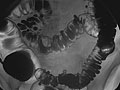

A barium enema is an X-ray exam of the large intestine (colon and rectum). It may also be called a lower gastrointestinal (GI) exam. The test is used to help find diseases and other problems that affect the large intestine. The colon is filled with a contrast material that contains barium so that the intestine can be seen on an X-ray. This is done by pouring the contrast material through a tube inserted into the anus. The barium blocks X-rays. This causes the barium-filled colon to show up clearly on the X-ray picture.

• In a single-contrast study, the colon is filled with barium. This outlines the intestine and shows large abnormalities.

• In a double-contrast or air-contrast study, the colon is first filled with barium, and then the barium is drained out. This leaves only a thin layer of barium on the wall of the colon. The colon is then filled with air. This provides a detailed view of the inner surface of the colon. It makes it easier to see narrowed areas (strictures), diverticula, and swelling.

The colon is filled with a contrast material that contains barium so that the colon can be seen on an X-ray. This is done by pouring the contrast material through a tube inserted into the anus. The barium blocks X-rays, causing the barium-filled colon to show up clearly on the X-ray picture.